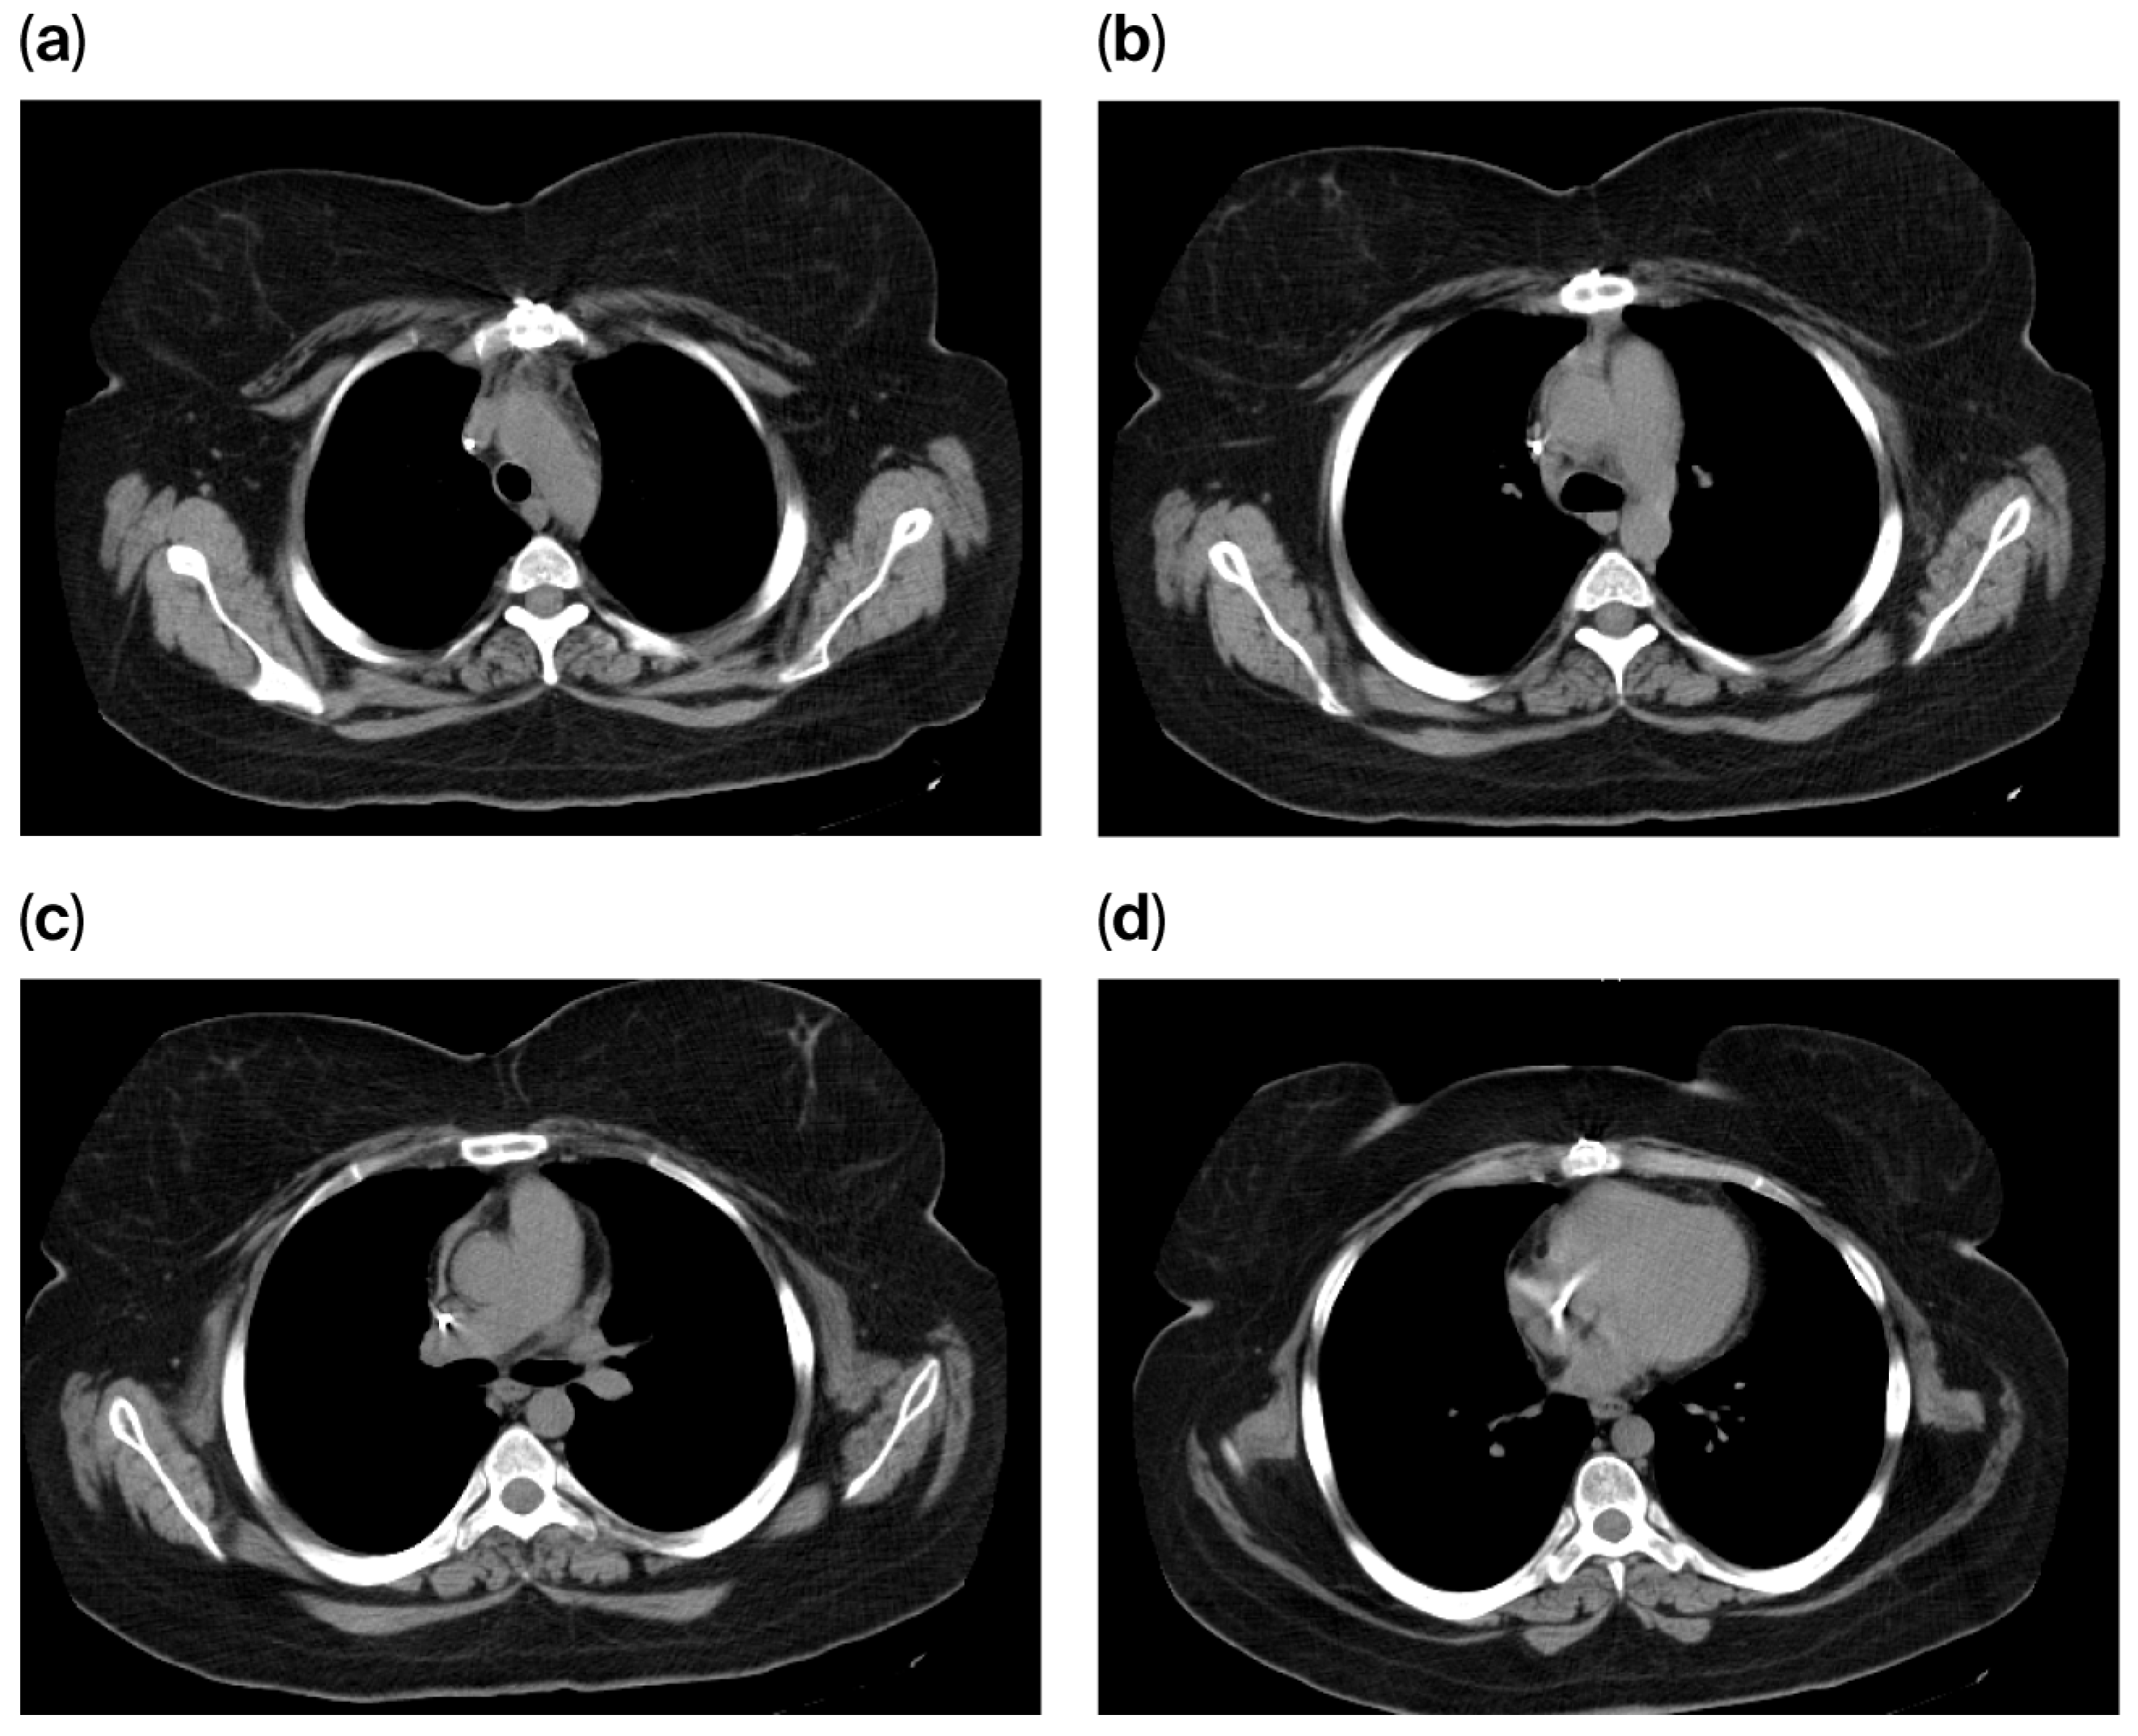

Follow-up imaging studies, including chest CT scans performed in August 2014 and February 2015, demonstrated no evidence of mediastinal, hilar, or axillary lymphadenopathy.

The chest CT scan performed in May 2016 demonstrated sternal cerclage with no evidence of suspicious lesions within the pulmonary parenchyma. No suspicious mediastinal, pleural, or pulmonary abnormalities were identified, and the visualized portions of the liver, pancreas, and spleen appeared unremarkable. Furthermore, no suspicious lesions were noted within the visualized skeletal segments, leading to the conclusion of a normal postoperative CT appearance (Figure 8).